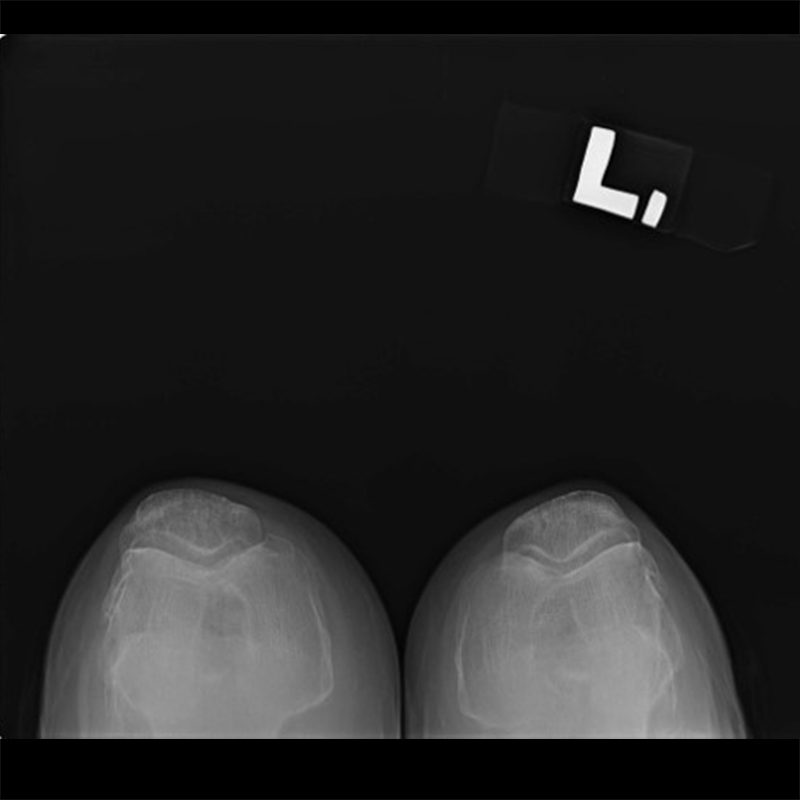

機器手臂手術 首頁 案例分享 膝關節手術 機器手臂手術 蔡女士 78歲 術前 術後 陳女士 70歲 術前 術後 術前 術後 ANGEVINE女士 73歲 術前 術後 U.S.A Mark 73歲 術前 術後 藍女士 78歲 術前 術後